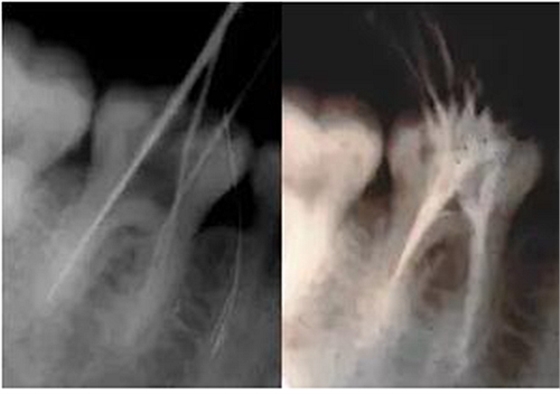

3、根管口的直線通道:特別對(duì)于彎曲根管!預(yù)備根管之前是否重視這個(gè)環(huán)節(jié),盡管找到了根管口,銼也能順利進(jìn)入根管,但根管口的直線通道是否建立也是衡量醫(yī)生操作技能的重要依據(jù)。

方法很多:手動(dòng)器械操作時(shí)我們可以采用價(jià)格便宜的“GG”鉆,PROTAPER機(jī)動(dòng)預(yù)備時(shí)可以采用SX銼。

圖7彎曲根管冠部處理之前 圖8用GG鉆或SX銼進(jìn)行預(yù)備

圖9處理后形成的直線通道

我的病例1_冠部處理成直線通道后的充填效果

我的病例2_下頜7"C"型根管的充填效果